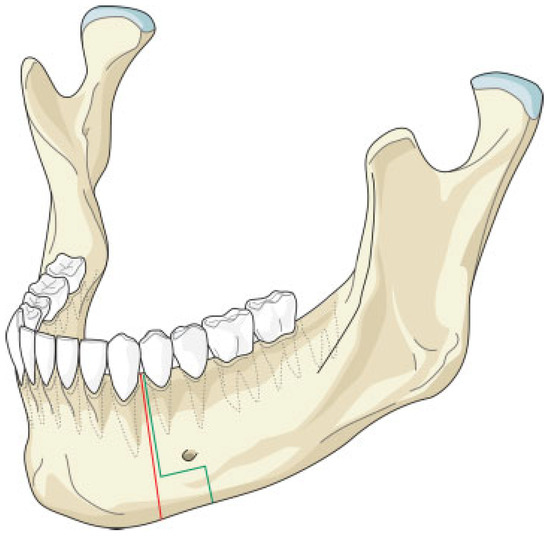

The mandibular resection is performed utilizing a horizontal osteotomy (Figure 1) above the mandibular angle on one side and a stepped body or angle osteotomy on the other side (Figure 2). A silicone template is created to the shape and dimension of the resected mandibular segment. The template is used as a guide to osteotomize the fibula at the donor site to reproduce the middle symphyseal segment of the mandible without shortening the fibula. The flap is then transferred to the recipient site and oriented so that one end will fit in the stepped osteotomy in a key and lock fashion (Figure 3) and the other end of the flap will overlap with the horizontal mandibular osteotomy (Figure 4), allowing room for adjustment in the anterior posterior direction to achieve the desired chin point projection (Figure 5). When the desired projection is achieved—guided by the silicone template—both ends of the flap are marked with a sterile pencil and trimmed using the saw; then miniplates are used to fix the flap in place (Figure 6).

Our technique is unique as it allows flexibility in adjusting the chin point projection to give the best possible aesthetic outcome. Trimming of the flap ends is performed at the recipient site to reduce the risk of short flap, but should this happen, the overlap at the horizontal osteotomy side will allow for compensation (Figure 4). Moreover, the greater surface contact area at the horizontal osteotomy side together with the key and lock fitting at the stepped osteotomy side (Figure 3) increase the stability of the flap and reduce the risk of rotation, hence allowing the use of miniplates for fixation; this in return allows room for placing more than one plate on each side, adding to the stability. The use of miniplates for fixation also facilitates the placement of implants in future rehabilitation.

Figure 1. Illustration of the horizontal osteotomy cuts (green lines). The red lines represent the conventional osteotomy cuts without the modification.